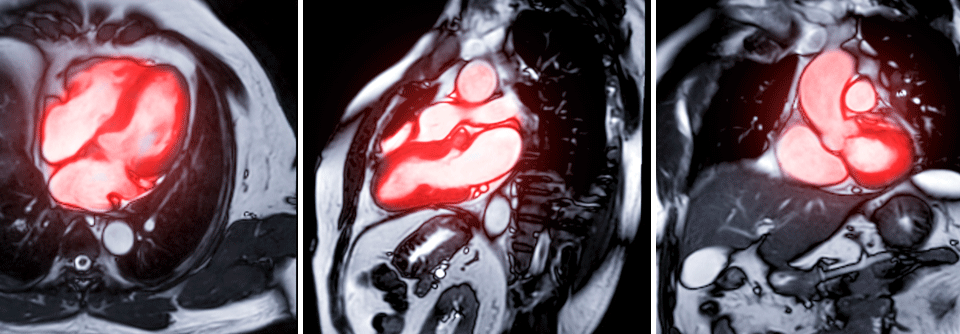

Einige antidiabetische Substanzklassen können mehr als nur den Blutzucker zu senken. Einige antidiabetische Substanzklassen können mehr als nur den Blutzucker zu senken. © iStock/HATICE GOCMEN

Menschen mit Typ-2-Diabetes haben bekanntlich ein deutlich erhöhtes Risiko für koronare ­Herzkrankheit (KHK) und Herzinsuffizienz. Diese kardialen ­Erkrankungen sollten auch bei der Wahl der medikamentösen Therapie ­berücksichtigt werden.